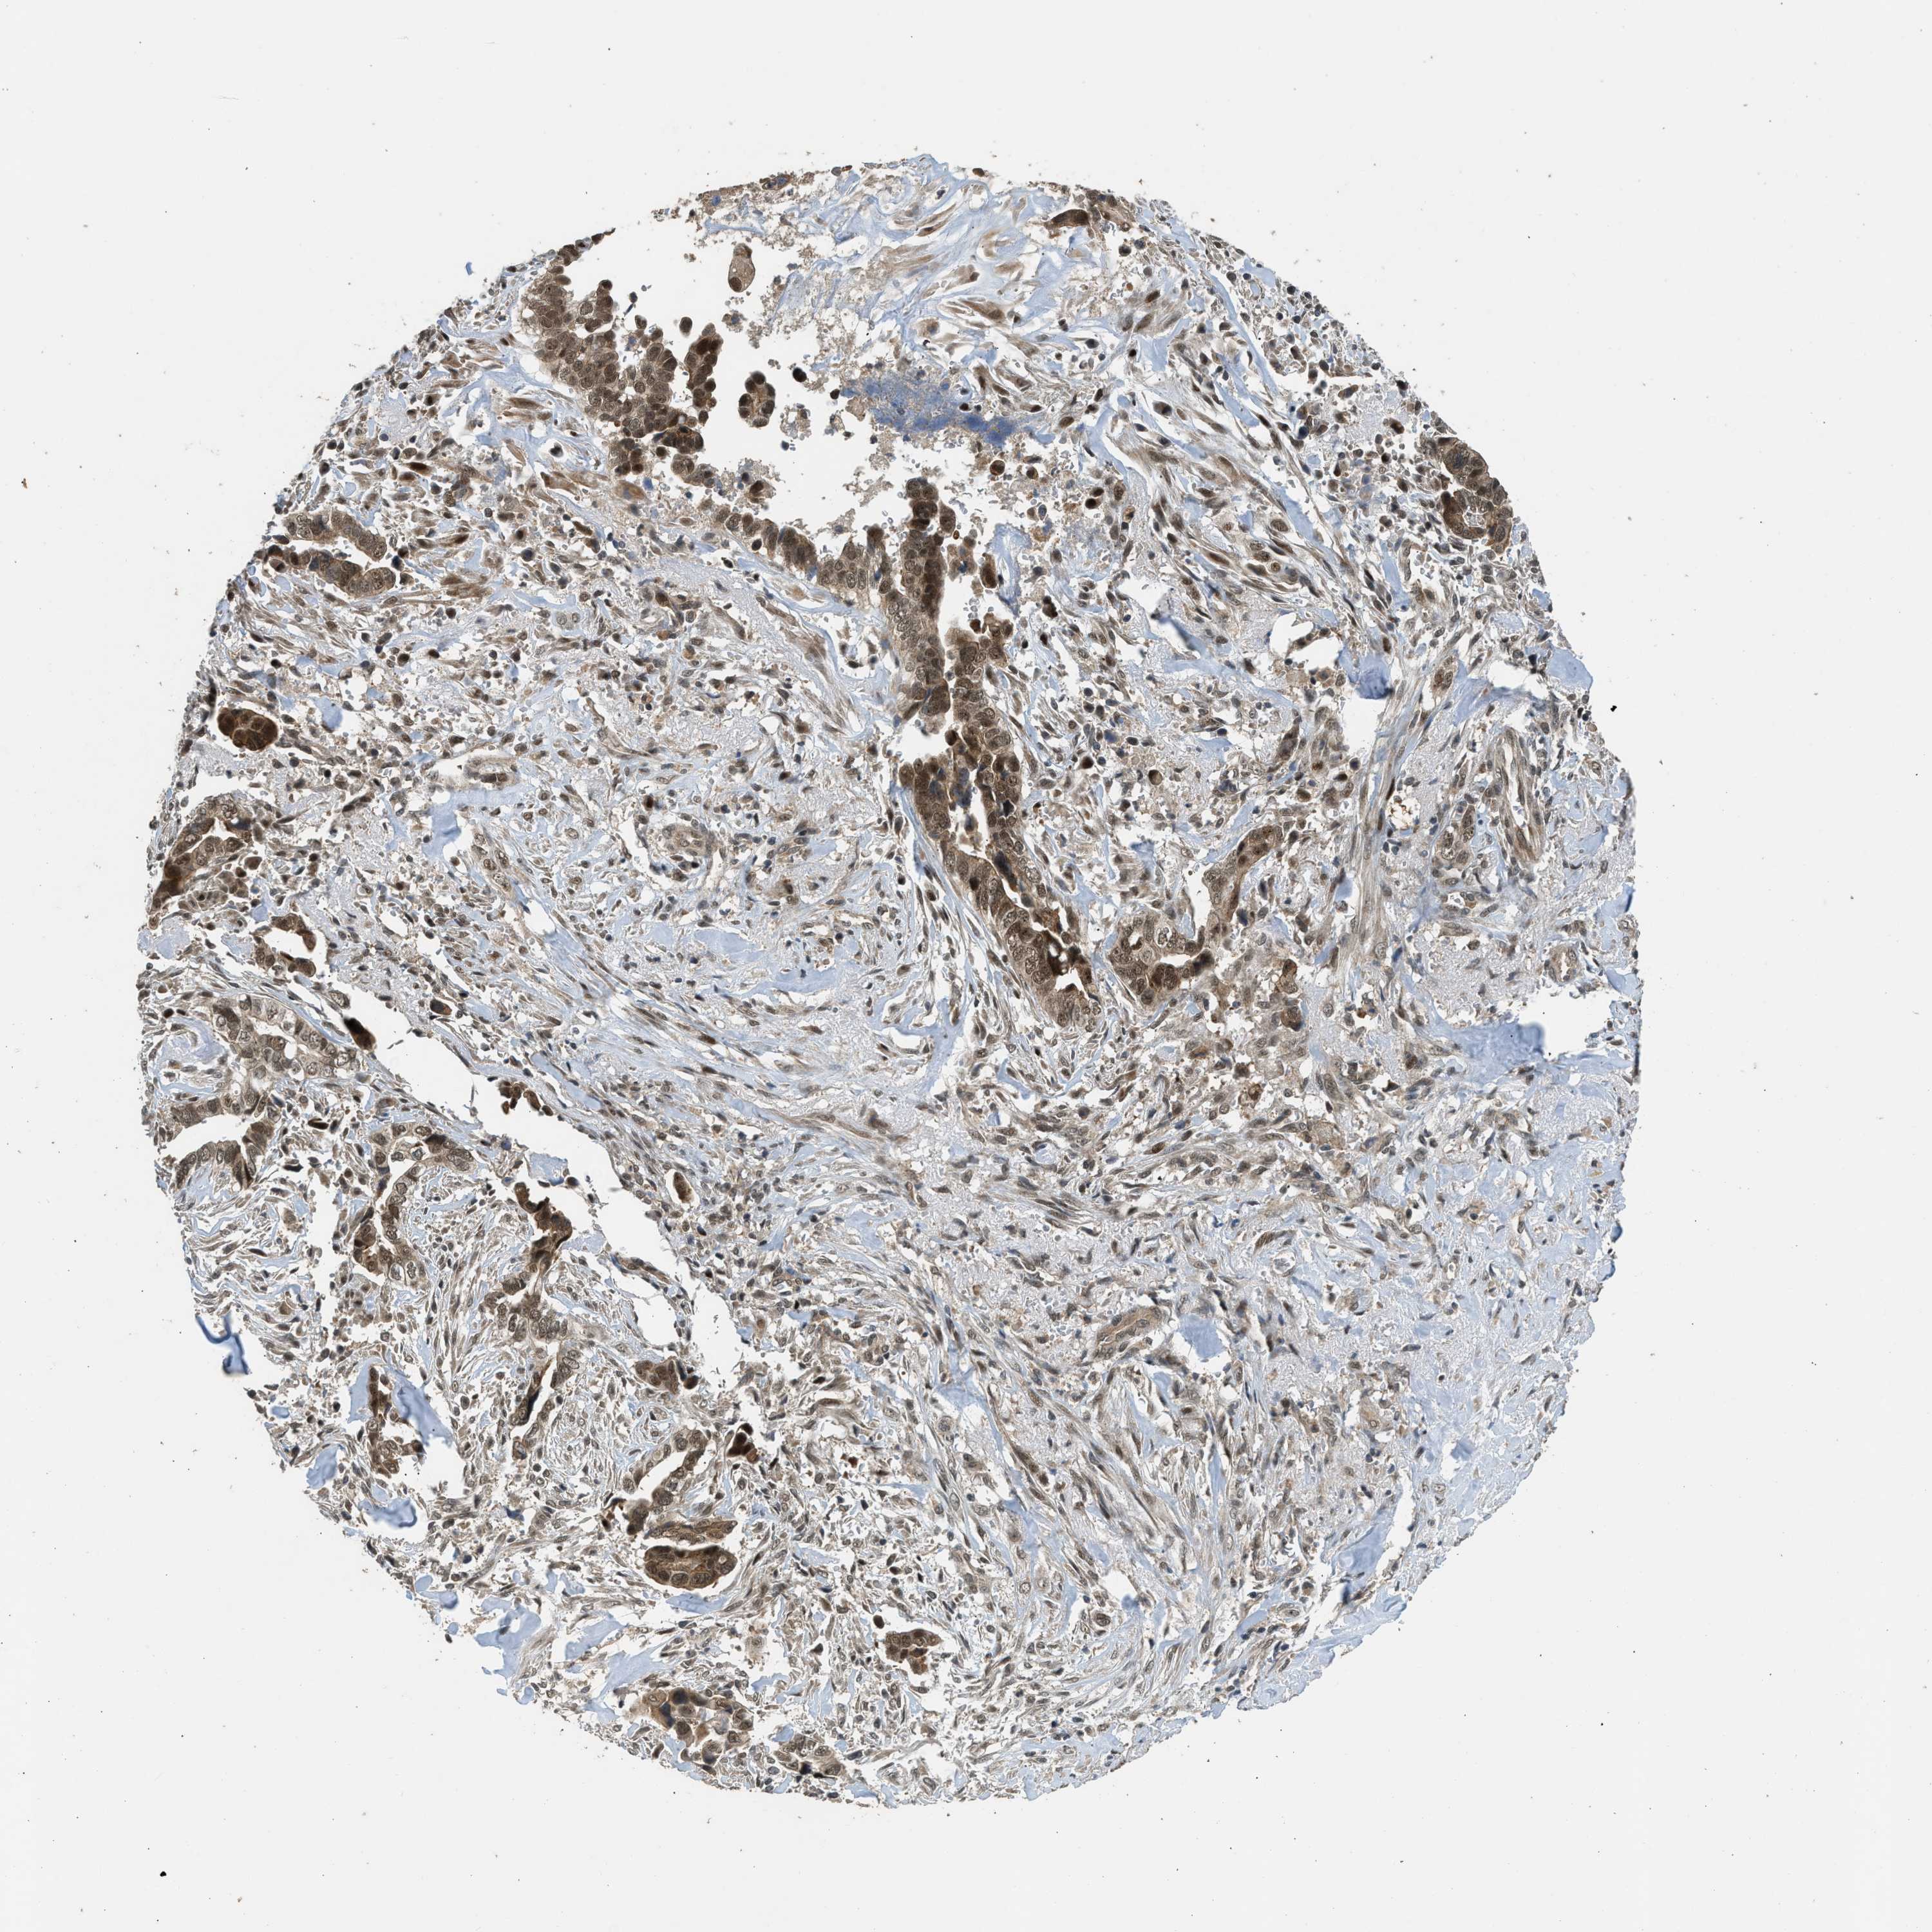

LIVER CANCER - Protein expressioni

A mouse-over function shows sample information and annotation data. Click on an image to view it in a full screen mode. Samples can be filtered based on level of antibody staining by selecting one or several of the following categories: high, medium, low and not detected. The assay and annotation is described here.

Note that samples used for immunohistochemistry by the Human Protein Atlas do not correspond to samples in the TCGA dataset.

Antibody stainingi

Antibody staining in the annotated cell types in the current human tissue is reported as not detected, low, medium, or high, based on conventional immunohistochemistry profiling in selected tissues. This score is based on the combination of the staining intensity and fraction of stained cells.

Each image is clickable and will lead to virtual microscopy that enables deeper exploration of all samples and also displays staining intensity scores, fraction scores and subcellular localization as well as patient and tissue information for each sample.

Antibody HPA018527

Staining

High

Medium

Low

Not detected

Intensity

Strong

Moderate

Weak

Negative

Quantity

>75%

75%-25%

<25%

None

Location

Nuclear

Cytoplasmic/membranous

Cytoplasmic/membranous,nuclear

Cholangiocarcinoma

Carcinoma, Hepatocellular, NOS